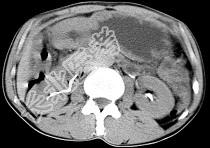

- 单项选择题男,56岁, 无规律上腹痛,左锁骨上淋巴结肿大, 消瘦、乏力,影像检查如图, 最可能的诊断是 ( )

C、胃癌并盆腔种植